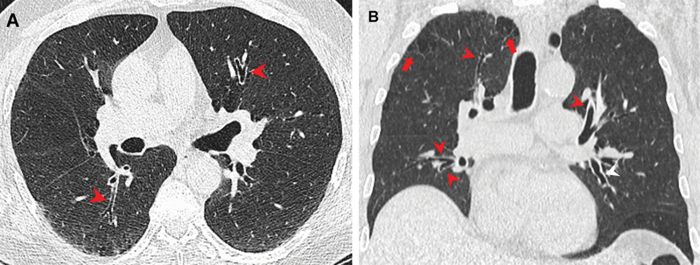

The findings, published in Radiology , examined the chest CT examinations of 56 marijuana smokers, 57 non-smokers and 33 tobacco-only smokers between 2005 and 2020. They determined higher rates of paraseptal emphysema and airway inflammatory changes, such as bronchiectasis, bronchial wall thickening, and mucoid impaction, in the marijuana smokers.

“I can tell if someone is a heavy or a long-time cigarette smoker when I look at a CT scan. With marijuana being the second most inhaled substance after tobacco, I started wondering: What does marijuana inhalation look like on a CT scan? Would I be able to tell if someone was a marijuana smoker, is it different from cigarette smoke?” says Revah, a radiologist The Ottawa Hospital, where the research was conducted.

Despite the small sample size, Revah’s findings suggest that marijuana smokers saw additional effects on the lungs above tobacco alone, including more instances of large and small airways diseases.